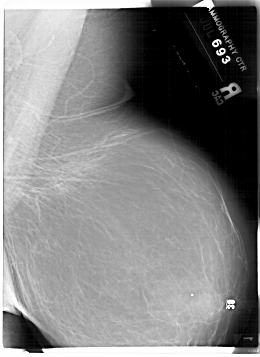

A_1882_1.RIGHT_CC

RIGHT_CC LINES 6706 PIXELS_PER_LINE 4636 BITS_PER_PIXEL 12 RESOLUTION 43.5 NON_OVERLAY